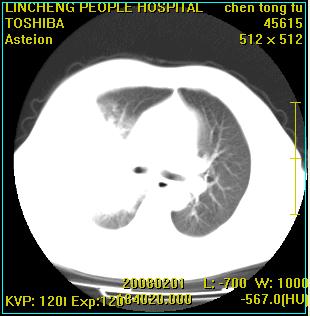

患者,男性,62岁。主因头晕,发热,咳嗽6天,高热达39度,esr19mm/h,wbc 3.9×10 9/l

大叶性肺炎并胸膜炎

右肺大叶性肺炎,胸腔积液。建议痰检。

实变区见空气支气管征,支气管通畅,考虑为大叶性肺炎,右侧少量胸水

1)考虑为:右肺感染性病变。建议:抗炎治疗复查。2)右侧少量胸腔积液。

考虑为右肺大叶性肺炎,胸腔积液,建议必要时纤维支气管镜检查,以排除肿瘤性病变。

右肺炎症并右侧胸腔少量积液。

考虑为右肺大叶性肺炎伴少量胸腔积液,建议复查,如病变不吸收或吸收不明显,建议纤维支气管镜检查,除外细支气管肺泡癌的可能。

右侧大叶性肺炎,右侧少量胸腔积液.

实变区见空气支气管征,支气管通畅,考虑为大叶性肺炎,右侧少量胸水。